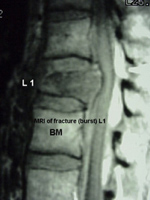

La RM brinda una imagen tridimensional y muy detallada de la columna. La médula espinal, las raíces nerviosas y los espacios están claramente definidos.

Esta RM de muestra detecta una fractura espinal